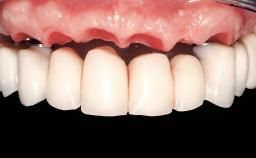

Immediate Loading of Eight Implants in the Maxilla and Six Implants in the Mandible and Final Restoration with Three-Unit and Four-Unit FDPs

Prosthesis Type FDP

Defining Characteristics Fully edentulous upper jaw to be rehabilitated with an implant-borne fixed dental prosthesis

Provisional Implant-Supported Prosthesis Prosthodontic margin < 3 mm apical to mucosal crest Prosthodontic margin < 3 mm apical to mucosal crest